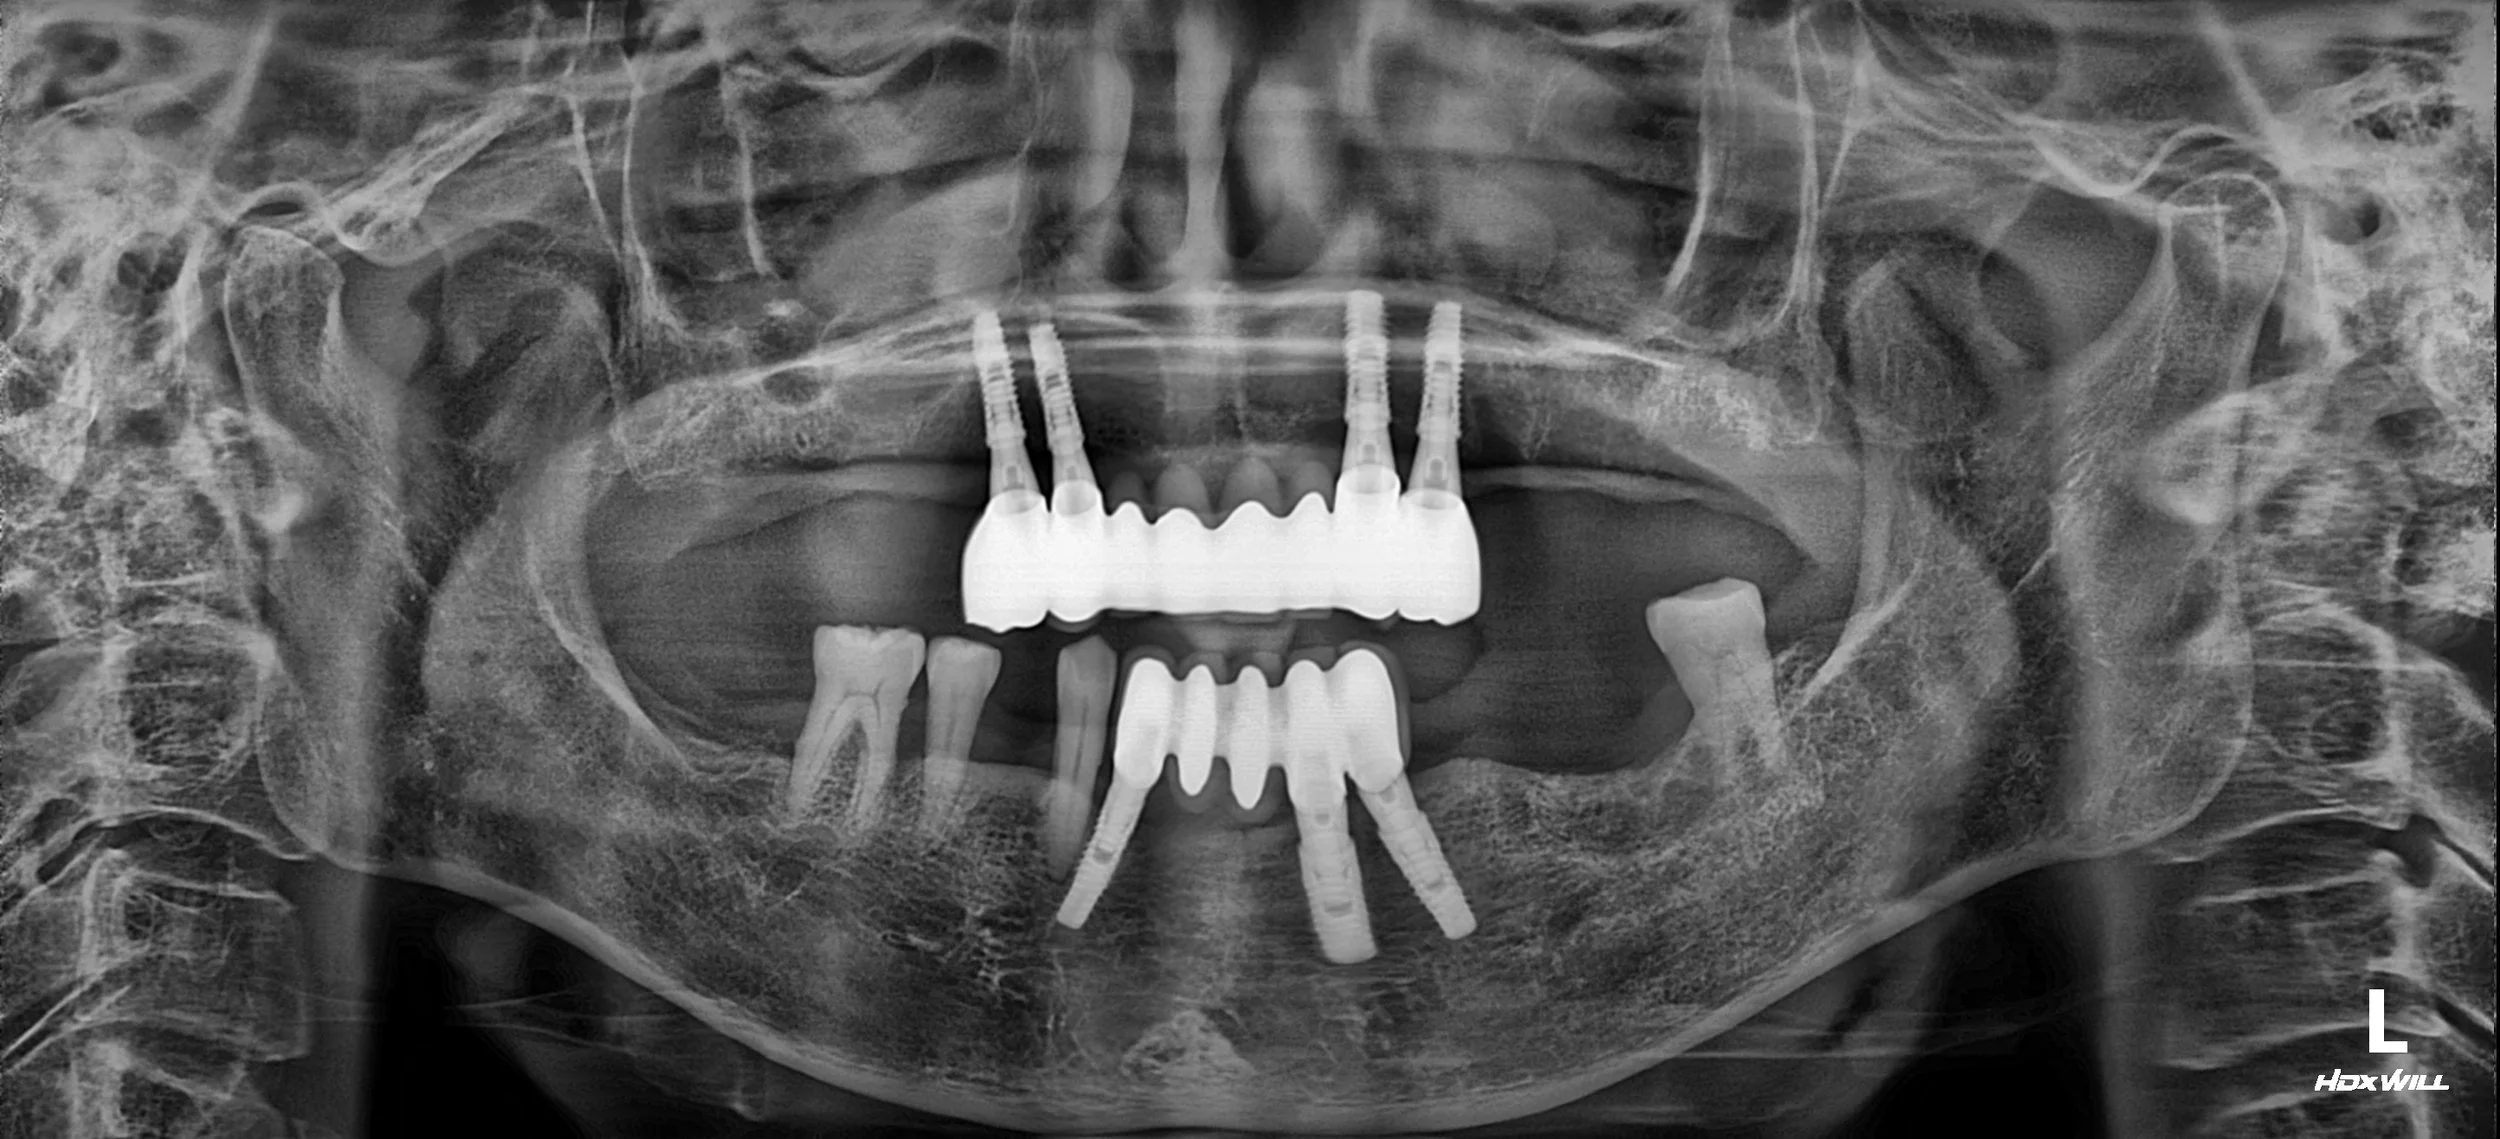

OPG - BEFORE